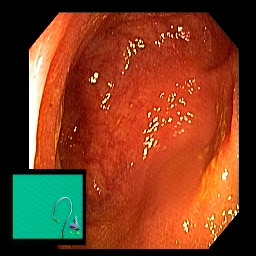

The performance metrics for Edgeconnect and AOTGAN on the validation data after fine-tuning the models, are shown in Table II. In addition to qualitative evaluation, Figure 3 provides example data from the different steps of the PolypConnect pipeline using the EdgeConnect model and the AOTGAN model. Due to obvious visual differences in the generated polyps between the models, we selected the EdgeConnect model as the main polyp inpainting model of the PolypConnect pipeline for further evaluation and qualitative assessment by domain experts.

Figure 3: Sample data used and generated in the different steps of PolypConnect pipeline. (a) - real polyp images, (b) - manually annotated polyp masks, (c) - randomly selected colon images used as input to the final step of PolypConnect, (d) - extracted edge images of row c. (e) - extracted edge images of polyp regions of row a using the masks of row b. (f) - combined edge images of row d and f. (g) - generated polyp on the images of row c using EdgeConnect. (h) - generated samples from AOTGAN.